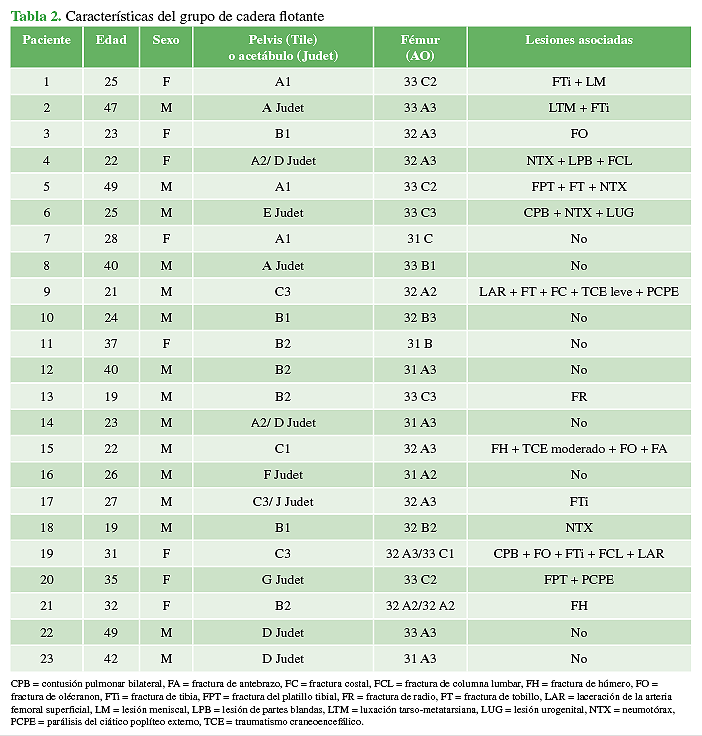

La mediana de los procedimientos traumatológicos realizados por paciente fue de 5 (rango 4-5). La mediana del tiempo de espera para la resolución total de la CF fue de 12 días (rango 2-54) principalmente demorado por el estado clínico-hemodinámico del paciente. En el momento del alta, 17 (73,9%) pacientes no tenían dolor y dos (8,8%) presentaban una lesión del nervio ciático poplíteo externo, que remitió por completo en ambos casos, a los seis y ocho meses de la cirugía. El 56,5% (n = 13) sufrió lesiones asociadas (Tabla 2).